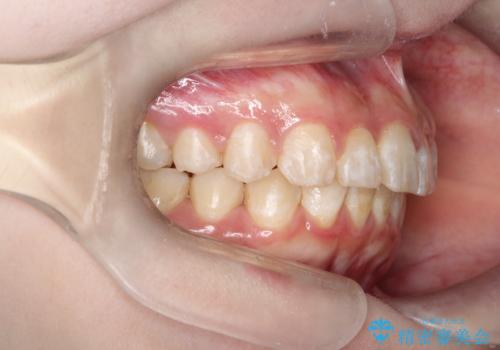

インビザラインで前歯のガタガタをきれいな歯並びへ

- 前歯のガタガタが気になるとのことで来院されました。

上顎の前歯の叢生があったのと、下あごの前歯が通常より1本欠損(先天欠損)していました。

上顎の歯と歯の間をわずかに削りスペースをつくり、並べる計画としました。インビザライン治療を選択されました。

しっかりとインビザラインを使用していただけたので、スムーズに治療を終了させることができました。